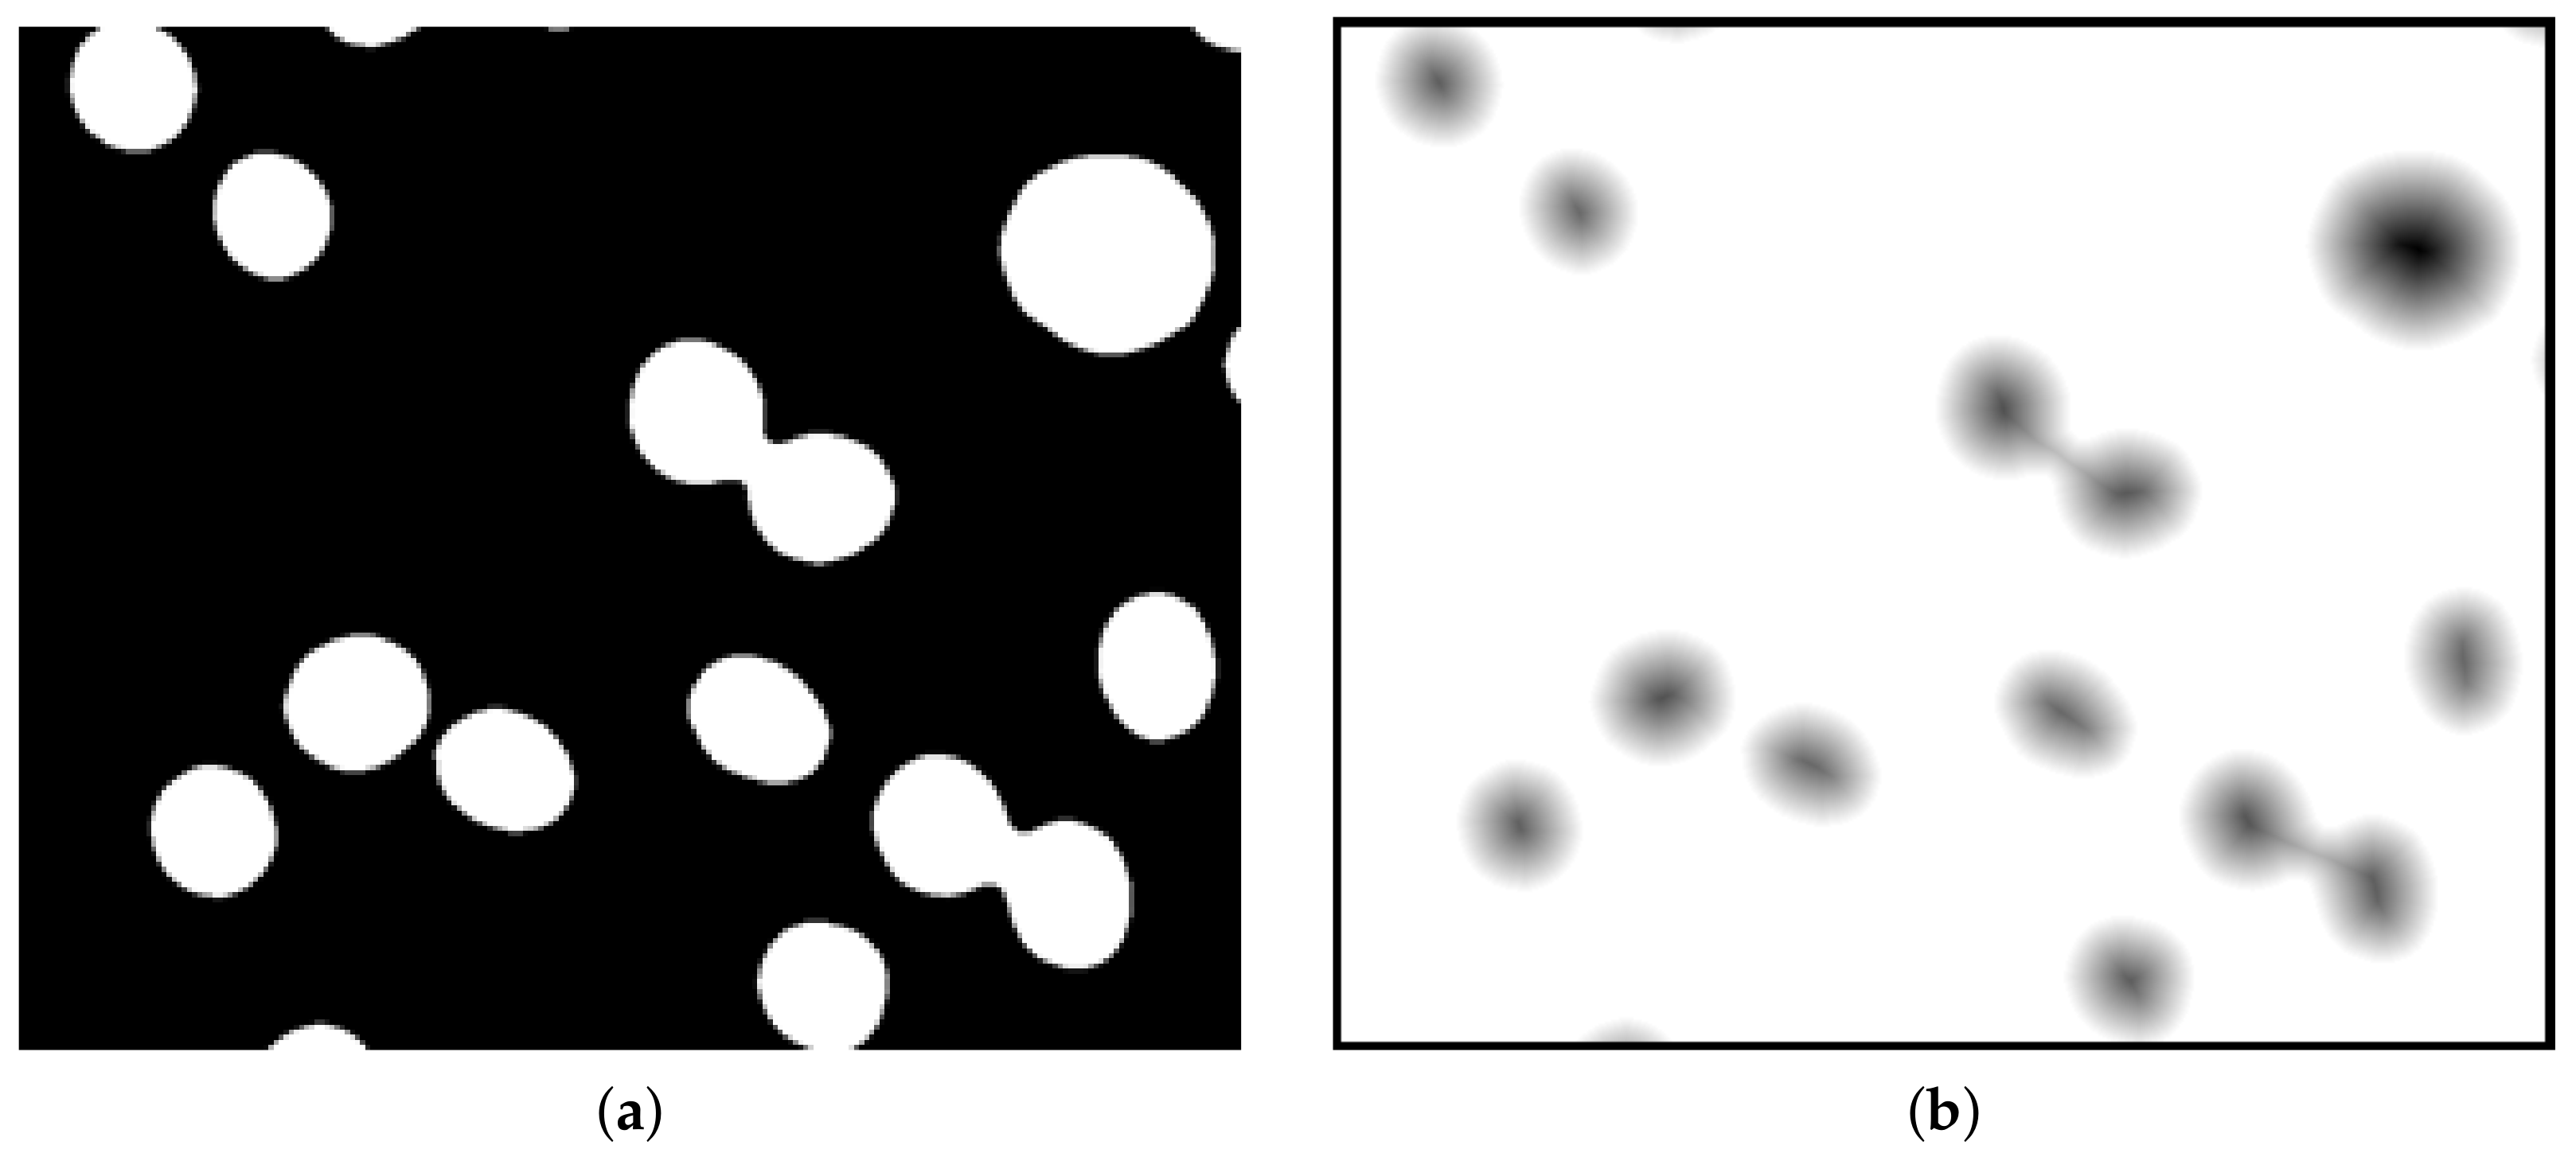

2.3. Distance Map

3. The Proposed Methodology